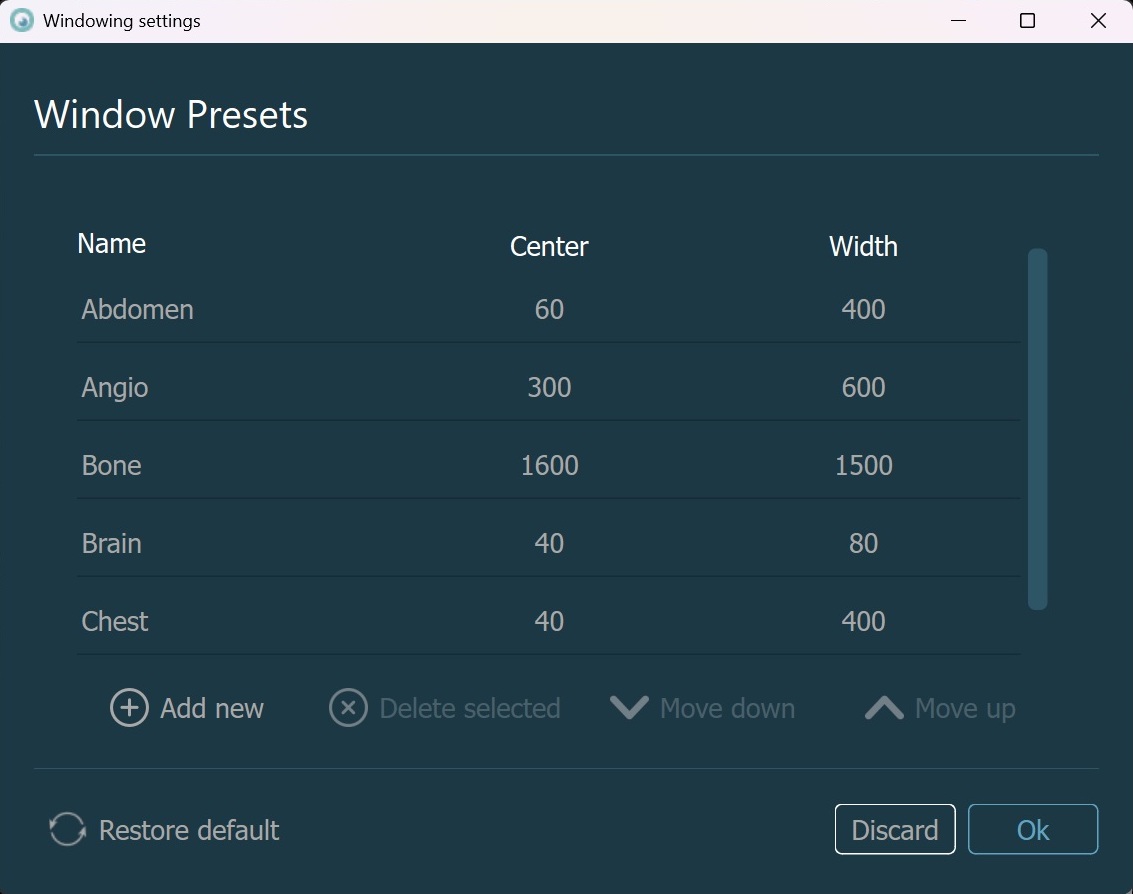

Windowing Settings¶

The windowing presets can also be modified directly by the CT Viewer. To open the windowing preset settings, select the Settings option from the windowing menu.

Confirm the changes to the windowing presets by pressing the OK button, or discard any changes by pressing the Discard button. Press Restore Default to restore the default windowing presets. The changes to the windowing presets

will update the settings of the software as well.

Modify an existing preset by double-clicking on the corresponding field, marking it as editable. Specify the new value and press

Enteror click outside of the field to finalize the modification.To add a new preset, press the

Add newbutton, which will add a new entry into the preset list. Follow the steps from the modify section to update the newly added preset.To delete a preset, select it from the list and press the

Delete selectedbutton.Reorder presets by selecting them for the list and pressing on one of the

Move uporMove downarrows. This changes the order in which the presets appear when you open them in the viewers.